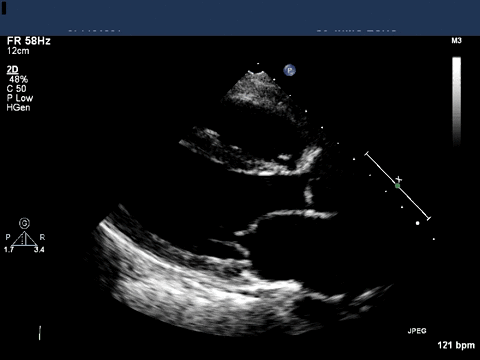

A transthoracic echocardiogram was obtained.